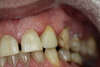

Homme de 48 ans souhaitant se débarrasser de ses couronnes en or devenues passées de mode et au niveau desquelles la gencive s’était rétractée, traité en 1 séance.